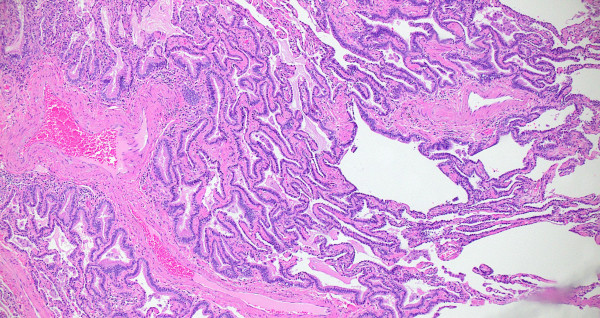

Compute tomography (CT) scan of the chest showed subpleural and peribronchial fibrosis with air-trapping on expiratory phase. The findings were read as likely “non-IPF pattern.” A serum antibody panel for hypersensitivity pneumonitis was positive for antibodies to Aspergillus flavus. Histologic sections of her lung biopsy demonstrated airways with peribronchiolar fibrosis with extensive metaplastic changes (Figure 1). Intra-alveolar giant cells and histiocytes with cholesterol clefts were seen (Figures 2-3). There were areas of interstitial inflammation and fibrosis resembling a cellular non-specific interstitial pneumonia (NSIP) pattern of injury (Figure 4). Also seen were extensive peribronchiolar metaplasia, microscopic “honeycombing”, interstitial giant cells, and poorly-formed granulomata (Figures 5-7).